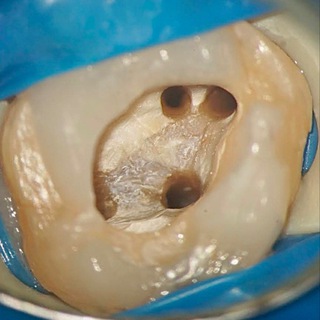

Endocactus MB2

Endodontics and Microsurgical endodontics